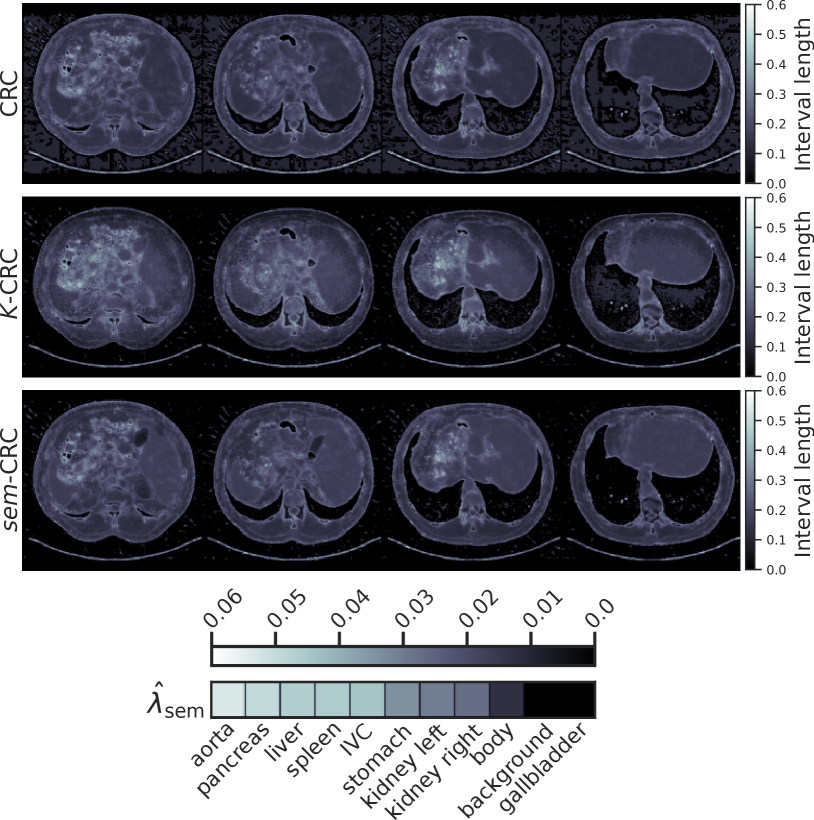

Refer to caption

(a) TotalSegmentator.

(b) FLARE23.

Figure 3: Mean interval length and risk stratified by organ for the FBP-UNet task across all calibration procedures and datasets. sem¯-CRC¯𝑠𝑒𝑚-CRC{\overline{sem}\text{-}{\text{CRC}}}over¯ start_ARG italic_s italic_e italic_m end_ARG - roman_CRC is the only procedure that guarantees risk control for each organ.

Table 1 summarizes risk and mean interval length across all datasets and tasks. All procedures are valid, i.e. they control risk at level ϵitalic-ϵ\epsilonitalic_ϵ. Our method, sem-CRC𝑠𝑒𝑚-CRC{sem\text{-}{\text{CRC}}}italic_s italic_e italic_m - roman_CRC, consistently provides the shortest uncertainty intervals. On the other hand, and as expected, controlling risk for each organ with sem¯-CRC¯𝑠𝑒𝑚-CRC{\overline{sem}\text{-}{\text{CRC}}}over¯ start_ARG italic_s italic_e italic_m end_ARG - roman_CRC increases the mean interval length. Fig. 2 compares the conformalized uncertainty maps obtained with each method on the same volume, and it includes the vector 𝝀^semsubscript^𝝀sem{\hat{\bm{\lambda}}}_{{\text{sem}}}over^ start_ARG bold_italic_λ end_ARG start_POSTSUBSCRIPT sem end_POSTSUBSCRIPT learned by sem-CRC𝑠𝑒𝑚-CRC{sem\text{-}{\text{CRC}}}italic_s italic_e italic_m - roman_CRC. The uncertainty maps generated by sem-CRC𝑠𝑒𝑚-CRC{sem\text{-}{\text{CRC}}}italic_s italic_e italic_m - roman_CRC are sharper and contain fewer artifacts thanks to using instance-level information. Furthermore, 𝝀^semsubscript^𝝀sem{\hat{\bm{\lambda}}}_{{\text{sem}}}over^ start_ARG bold_italic_λ end_ARG start_POSTSUBSCRIPT sem end_POSTSUBSCRIPT directly informs on which organs have higher levels of uncertainty, depicting how the same model may display different uncertainty patterns across different populations. These findings are fundamental to the responsible use of general-purpose machine learning models across centers serving diverse demographics. Finally, Fig. 3 highlights the difference between controlling risk for each organ or cumulatively over a volume: all methods but sem¯-CRC¯𝑠𝑒𝑚-CRC{\overline{sem}\text{-}{\text{CRC}}}over¯ start_ARG italic_s italic_e italic_m end_ARG - roman_CRC achieve risk control by overcovering background and undercovering organs. Our methodology gives users the flexibility to specify which organs they desire to control risk for depending on the clinical task at hand.